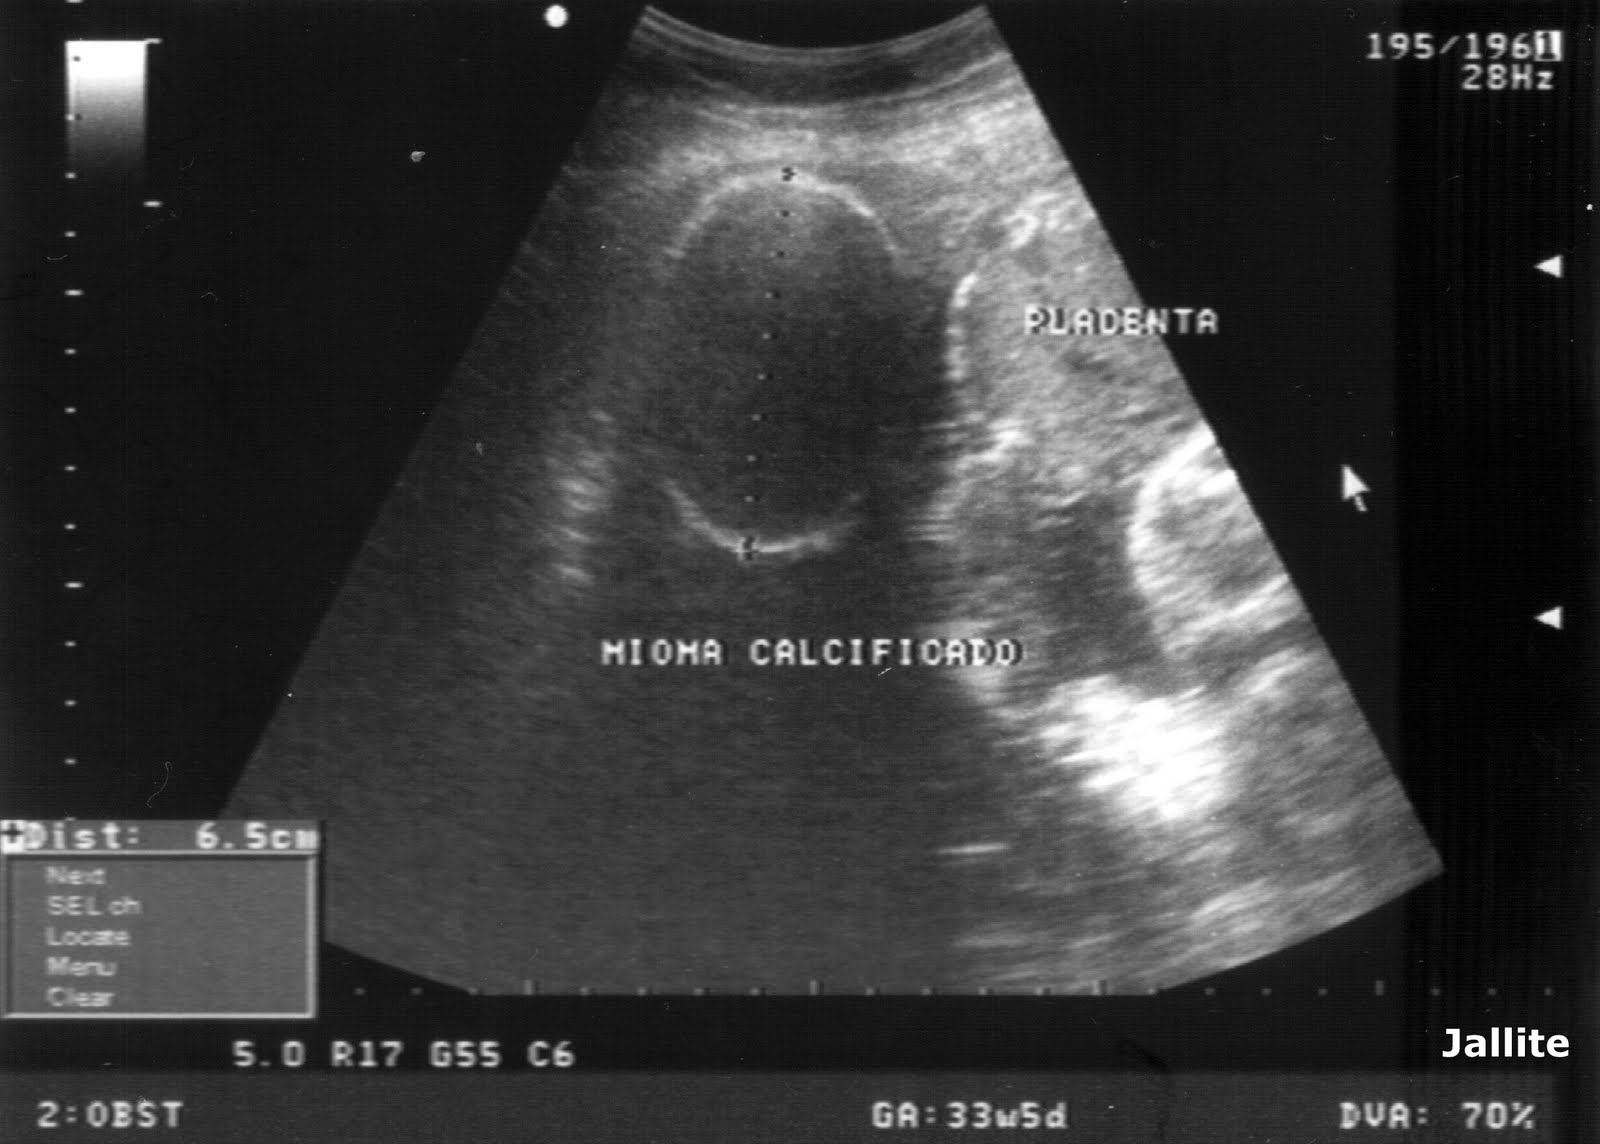

Mioma Calcificado & Embarazo & Placenta Hiper-madura

Webo aspeto ecográfico deste tipo de miomas é difícil de distinguir dos outros miomas, especialmente os que têm grandes dimensões. Esta situação deve ser distinguida da de. O mioma no útero é o tumor benigno mais frequente nas mulheres. Ele pode aparecer em diferentes locais e ter vários tamanhos. Webapenas a retirada do mioma e avaliação pelo patologista pode dar esse diagnóstico. A necrose e as calcificações não necessariamente significam que este mioma é maligno. Um mioma uterino (também designado por fibroide, leiomioma ou fibromioma) é um tumor benigno que cresce no tecido do útero, sendo muito raro malignizar. Não, os miomas são tumores benignos, ou seja, as células são semelhantes às do tecido normal e não têm a capacidade de provocar. Webo mioma intramural é um tipo de tumor benigno que pode provocar sintomas como dor, cólicas e alterações menstruais. Entenda melhor porque acontece, quais os sintomas,.